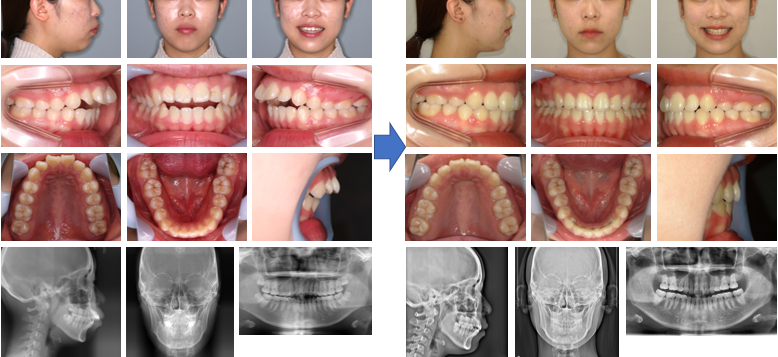

【治療例】初診時年齢:19歳7か月 / 性別:女性 / 主訴:咬み合わせ、たまに口が開かない

症例の概要:この症例は上下の咬み合わせが悪い事とたまに朝に口が開かない事を主訴に来院された。下顎前歯1本(右下2番)が先天性欠如のほか、両側第一小臼歯が鋏状咬合を呈していた。口元の突出感を認めたことから上顎両側第一小臼歯を抜歯した。その結果、開口障害も無くなり、口元の突出感や咬み合わせも改善した。

主訴: 咬み合わせ、たまに口が開かない

診断名: 両側第一小臼歯の鋏状咬合および下顎前歯1歯(右下2番)の先天性欠如を認めた上顎前突症例

使用した主な装置: マルチブラケット装置、歯科矯正用アンカースクリュー、顎間ゴム

抜歯/非抜歯および抜歯部位: 抜歯(上顎両側第一小臼歯)

治療期間:2年0か月

治療回数:30回

リスクの副作用:歯の移動や抜歯による違和感や疼痛、口内炎、歯肉退縮、歯根吸収が生じることがある